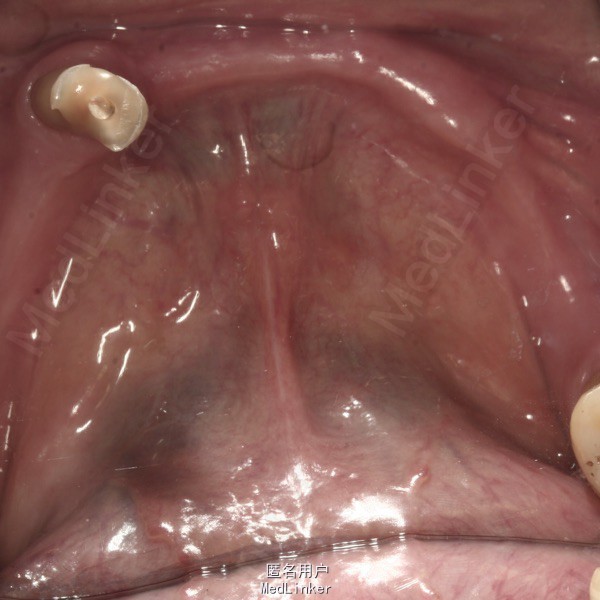

查体 辅查

上颌多颗前后牙缺失,下颌仅余留37和44。